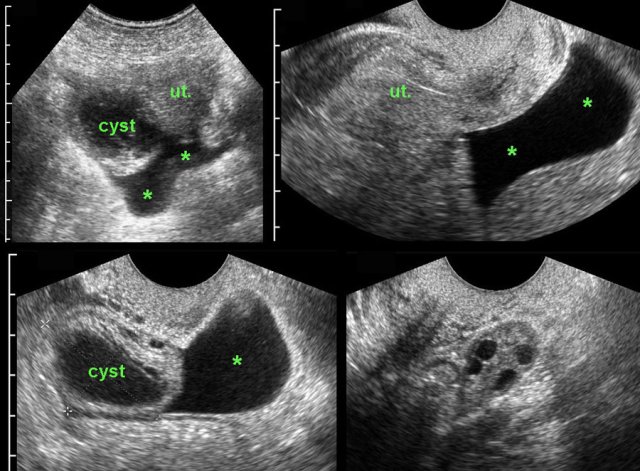

case 3

These images are of a woman of 17 years old with acute, severe RLQ pain. CRP 1.

US reveals an ill-defined thick-walled right ovarian cyst and free fluid (*) in Douglas pouch.

TVUS confirms the fluid and a partially collapsed,

easily compressible cyst in the right ovary.

The left ovary is normal (right lower

image).

The pain gradually decreased and lab-findings remained normal.

Within one week there was complete

normalization of the US findings.

The most likely diagnosis: ruptured functional cyst.

case 4

This functional, hemorrhagic cyst was a coincidental

finding and could easily be compressed against the promontory (p).

Complete resolution of the abnormalities within two weeks.